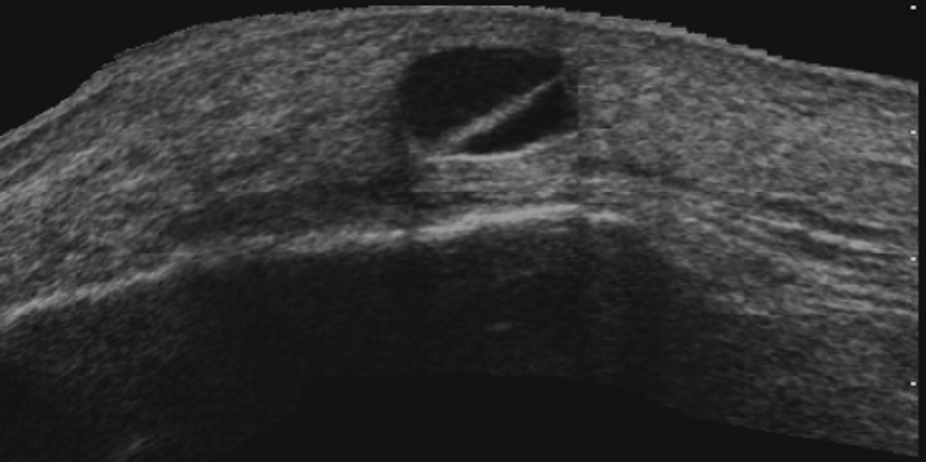

Interpretación especializada del sistema osteomioarticular

Nos enfocamos en la interpretación de ecografías de , tendones, músculos y articulaciones, lo que nos permite detectar con precisión cualquier anomalía o lesión en estas áreas.